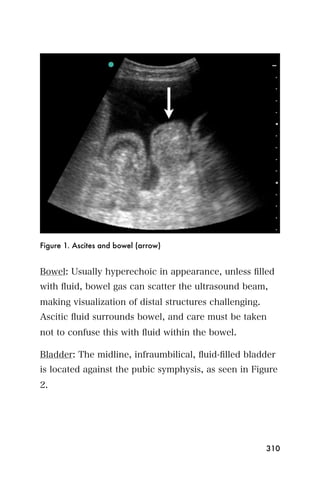

center that is the endometrium.

Figure 3. The bladder (*) and empty uterus (arrow)

An empty uterus may cause the clinician to worry about

an ectopic pregnancy. A ruptured ectopic pregnancy

blood may extend into the abdomen, so it is important

107